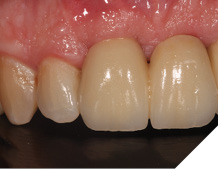

The definitive bridge was fitted and torqued in situ uneventfully after such excellent healing of the provisional bridge (Figs. 31-37).

Fig. 37

The definitive bridge has integrated well and both hard and soft tissue healing has gone well and very predictably. The chosen biomaterials have integrated well and healed exactly how we would expect them to. The patient was very happy with the aesthetic result especially when we consider what he had been used to preoperatively. The function and phonetics met the patient’s expectations and overall, we were all very happy with the result.